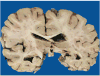

Context: Autopsy evaluation of the brain of a patient with frontotemporal dementia (FTD) can be daunting to the general pathologist. At some point in their training, most pathologists learn about Pick disease, and can recognize Pick bodies, the morphologic hallmark of Pick disease. Pick disease is a type of frontotemporal lobar degeneration (FTLD), the general category of pathologic process underlying most cases of FTD. The 2 major categories of pathologic FTLD are tauopathies (FTLD-tau) and ubiquitinopathies (FTLD-U). Pick disease is one of the FTLD-tau subtypes and is termed FTLD-tau (PiD).